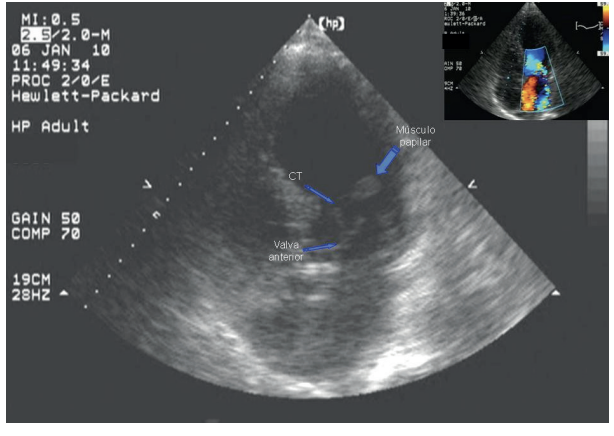

Origen anómalo de la coronaria izquierda en la arteria pulmonar

IMÁGENES EN CARDIOLOGÍA